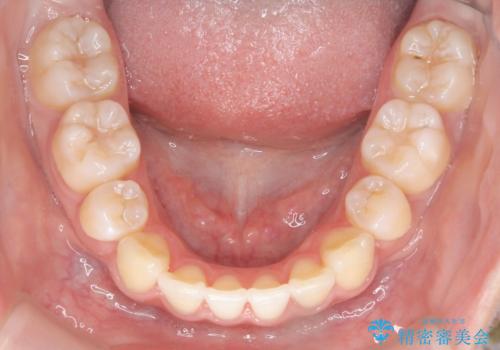

- ハーフリンガル

- 3年1ヶ月

- 出っ歯を治したいとのことで来院されました。

目立たない装置が希望とのことでハーフリンガルで治療をすることとしました。

ワイヤー矯正治療は、歯並びの問題を改善し、美しい笑顔を取り戻すための効果的な方法です。当院では経験豊富なスタッフが、患者様一人ひとりのニーズに合わせた最適な治療を提供しています。治療の詳細やご予約については、お気軽にお問い合わせください。